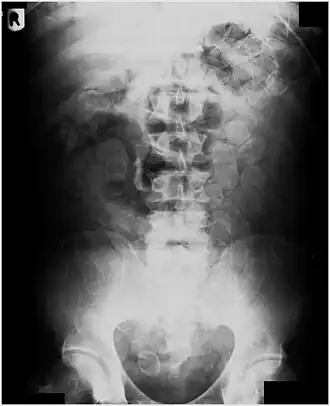

Abdominal X-ray showing small packages of cocaine swallowed by a trafficker.

Vibrator stuck in the rectum can be seen on this abdominal X-ray.